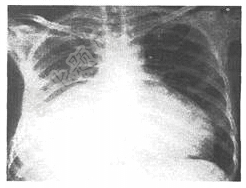

- 单项选择题患者,女,26岁,端坐呼吸、乏力、腹胀,心音遥远,胸部正侧位摄片示心影增大如图,最可能的诊断是( )。

A、心包积液

B、缩窄性心包炎

C、扩张性心肌病

D、肥厚性心肌病

E、风湿性心脏病二尖瓣狭窄